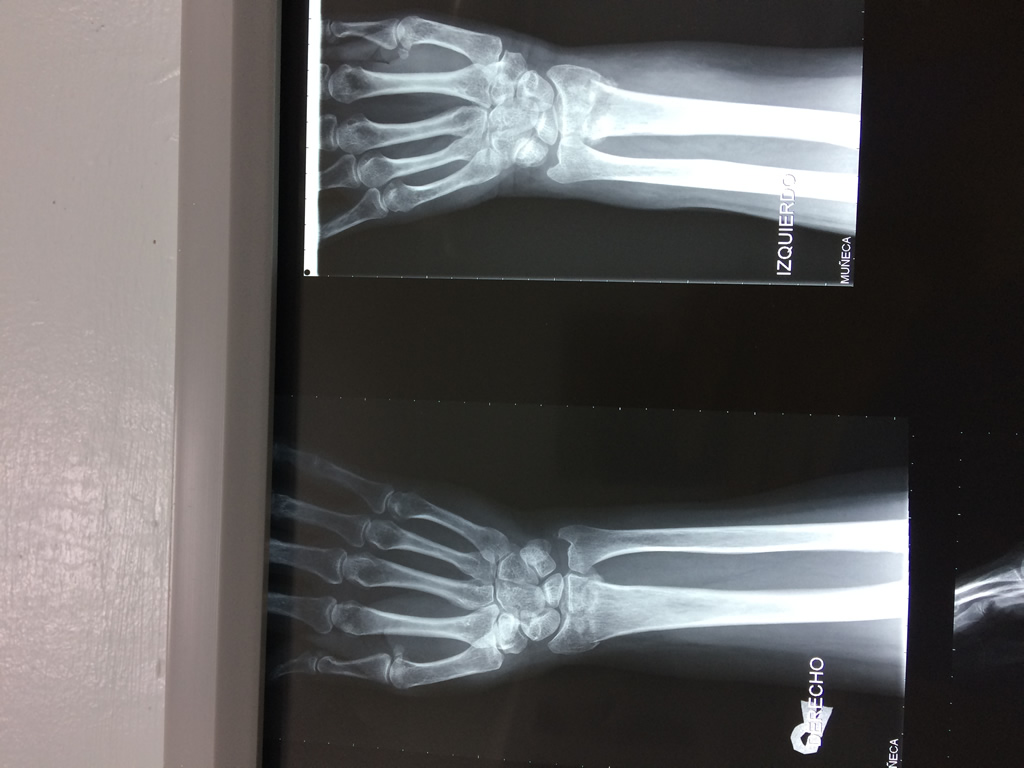

Cirugias en El Salvador - Cirugías de Muñecas y Manos

Los procedimientos más comunes en cirugía de la mano son aquellos destinados a reparar traumatismos, incluyendo lesiones de tendones, nervios, vasos sanguíneos, y articulaciones; huesos fracturados; y quemaduras, cortes, y otros daños de la piel.